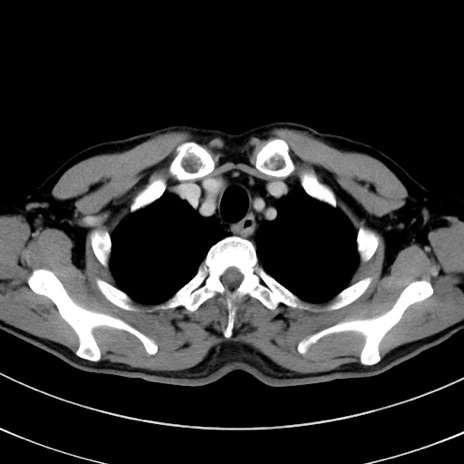

症例8(横断像)

【症例】 60歳代男性

【主訴】 黒色吐物

【現病歴】 4日前から嘔気自覚、2日前の朝食後にも嘔気あり、自分で手で嘔吐反射起こし嘔吐したところ血が混ざっていたため受診。

【既往歴】 5年前汎発性腹膜炎を伴う急性虫垂炎で手術、高血圧、前立腺肥大症、高脂血症

【身体所見】 腹部正中に手術癩痕あり 腹部平坦・軟圧痛なし膨満感あり

【データ】WBC 8400、CRP 4.54